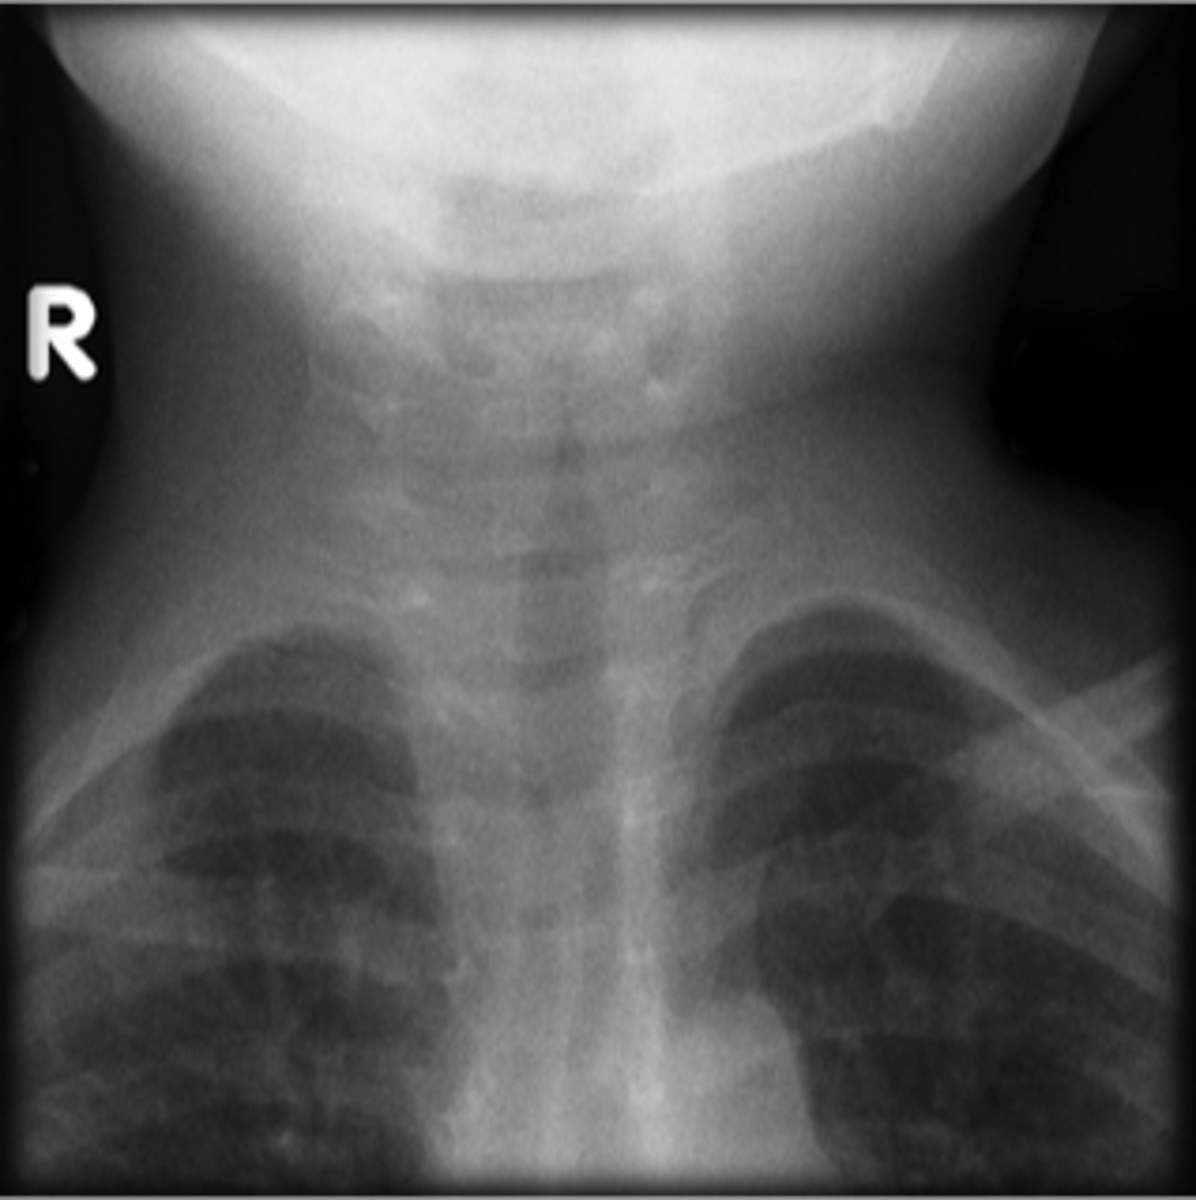

Epiglottitis (thumb sign)

steeple sign (croup)

steeple sign (croup)

Croup

Steeple sign- group